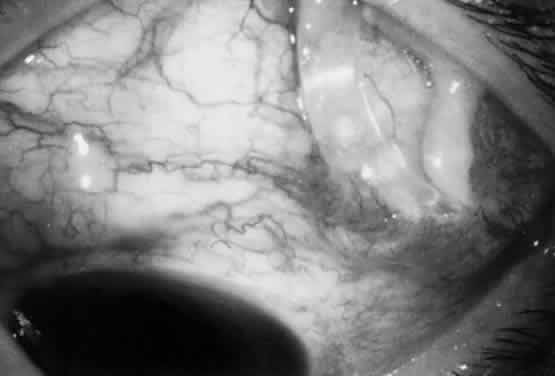

The filtration site is placed posteriorly near the equator in the latest generation of shunts. The morphologic features of these blebs are different from those of functional blebs at the limbus, as seen with a trabeculectomy. They are typically thick-walled, with prominent conjunctival vascularity, and are elevated over the reservoir (Fig. 1). Although the silicone tube and PMMA plates of the Molteno shunt are biologically inert and do not produce tissue necrosis, a thick fibrous capsule envelops the reservoir and tube (Fig. 2)25–29

Fig. 1. Thick vascular bleb over single-plate Molteno shunt.